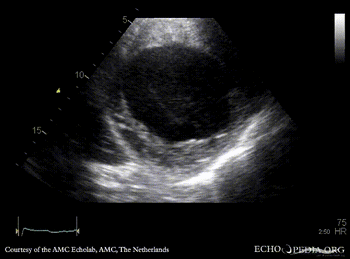

E00217.gif E00218.gif

PLAX: dilated left ventricle with poor function PSAX: dilated left ventricle with poor function, spontaneous echo contrast